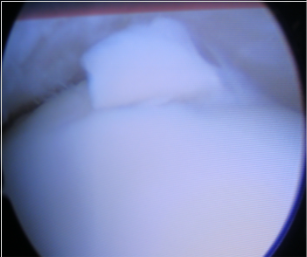

Cartilage lesion remediation, nanoperforations and Chondrofiller